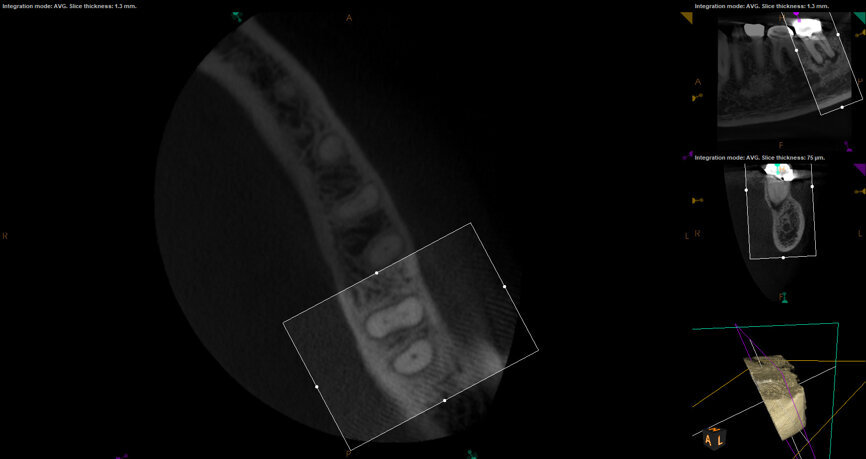

Fig. 17a: Case assisted with CBCT to determine anatomy pre-operatively. Note the multiple cross sections moving apically and the correlation to the 2-D view. Note also the conservative taper in relation to the root width. (Courtesy of Dr. Brett Gilbert)

Fig. 17b: Case assisted with CBCT to determine anatomy pre-operatively. Note the multiple cross sections moving apically and the correlation to the 2-D view. Note also the conservative taper in relation to the root width. (Courtesy of Dr. Brett Gilbert)

Fig. 17c: Case assisted with CBCT to determine anatomy pre-operatively. Note the multiple cross sections moving apically and the correlation to the 2-D view. Note also the conservative taper in relation to the root width. (Courtesy of Dr. Brett Gilbert)

Fig. 17d: Case assisted with CBCT to determine anatomy pre-operatively. Note the multiple cross sections moving apically and the correlation to the 2-D view. Note also the conservative taper in relation to the root width. (Courtesy of Dr. Brett Gilbert)

Fig. 17e: Case assisted with CBCT to determine anatomy pre-operatively. Note the multiple cross sections moving apically and the correlation to the 2-D view. Note also the conservative taper in relation to the root width. (Courtesy of Dr. Brett Gilbert)

Fig. 17f: Case assisted with CBCT to determine anatomy pre-operatively. Note the multiple cross sections moving apically and the correlation to the 2-D view. Note also the conservative taper in relation to the root width. (Courtesy of Dr. Brett Gilbert)

Managing complex anatomy is much simpler if the clinician has a pre-operative road map. The CBCT provides the roadmap and the surgical microscope the lens (literally) through which to visualize the result. Aside from a relaxed patient who is profoundly numb, being able to visualize anatomy by taking a pre-operative (and possibly intra-operative) CBCT and using a surgical microscope during treatment have no substitutes. They are the current “Gold Standard” in that 3-D imaging shows the clinician the true reality of a clinical situation as opposed to the suggestion gained from a 2-D radiograph. Proper interpretation of imaging prior to and/or during endodontic treatment goes a long way in taking the “guesswork” out of identifying canal location and other anatomical complexities as the procedure unfolds. In a 2014 study by El Fayad and Johnson, it was determined that when having a pre-operative CBCT as compared to 2-D radiographs alone, the treatment plan was modified 62 percent of the time. This is a huge game changer to think that the information learned from 3-D imaging changed the plan of treatment over six times out of 10 (Fig. 4).[2]